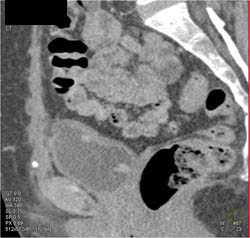

Bladder Cancer